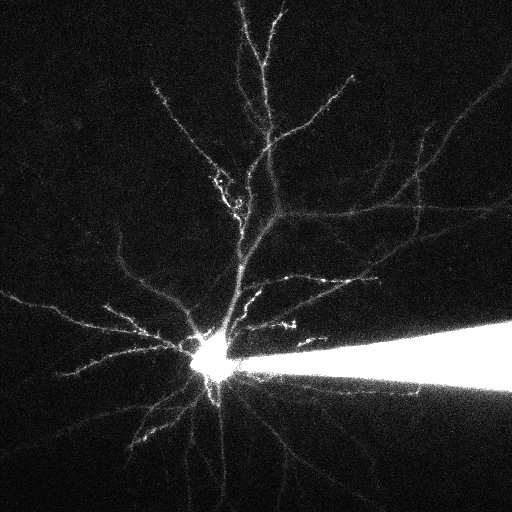

Trying to keep up with the literaturepic.twitter.com/I1JT0ZiWO0